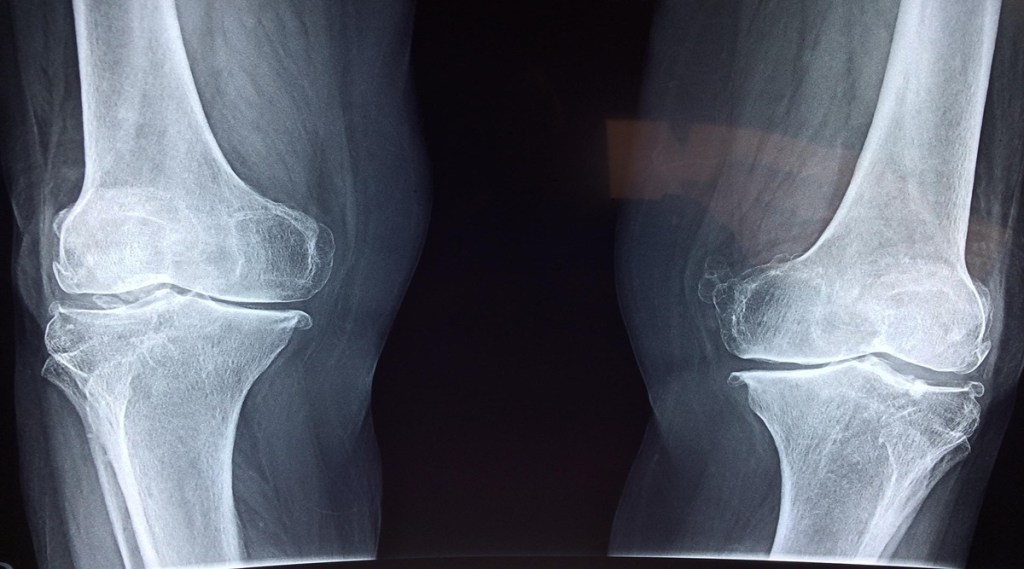

Every year on October 12 is marked as World Arthritis Day to raise awareness about arthritis and its impact on one’s health. Today we we present to you ways to keep your bones healthy that can help in preventing disorders like Arthritis or osteoporosis.

World Arthritis Day 2023: Bones are an extremely important component of the body as they support it and allow movement. Moreover, bones provide protection to the brain, heart, and other organs from injury.